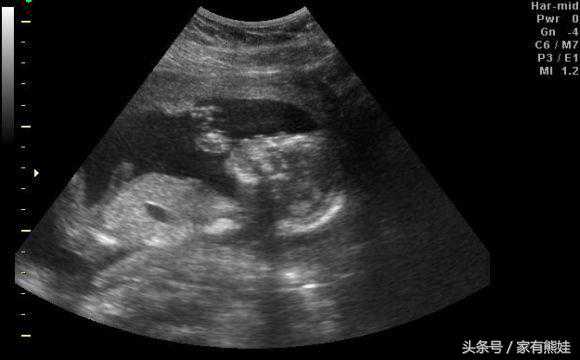

怀孕5个半月,今天找了熟人做了b超。医生指着两腿之间的部位,跟我说应该是弟弟,还让我看,当时也没看懂是什么样子的,后面他又跟我说了是弟弟,我的心反而更加坚定了。